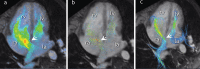

Materials and methods: Four-dimensional flow MRI examinations were performed at four institutions across Europe and the US. Twenty-nine patients (mean age, 43 years; 11 male) were included in the study. Flow measurements were performed at three levels (valve, main artery and periphery) in both the pulmonary and systemic circulation by two independent readers and compared against stroke volumes from 4D flow anatomic data. Further, the shunt ratio (Qp/Qs) was calculated. Additionally, shunt volume was quantified at the atrial level by tracking the atrial septum.

Results: Measurements of the pulmonary blood flow at multiple levels correlate well whether measuring at the valve, main pulmonary artery or branch pulmonary arteries (r = 0.885-0.886). Measurements of the systemic blood flow show excellent correlation, whether measuring at the valve, ascending aorta or sum of flow from the superior vena cava (SVC) and descending aorta (r = 0.974-0.991). Intraclass agreement between the two observers for the flow measurements varies between 0.96 and 0.99. Compared with stroke volume, pulmonic flow is underestimated with 0.26 l/min at the main pulmonary artery level, and systemic flow is overestimated with 0.16 l/min at the ascending aorta level. Direct measurements of ASD flow are feasible in 20 of 29 (69%) patients.